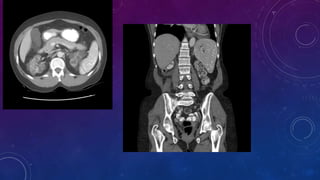

• Multiple pelvic phleboliths.

• Small well-defined round osseous lesions in the left

side of the abdomen, adjacent to midline represent

calcified lymph node in the para-aortic and left

common iliac groups, also visualized on the

corresponding CT.